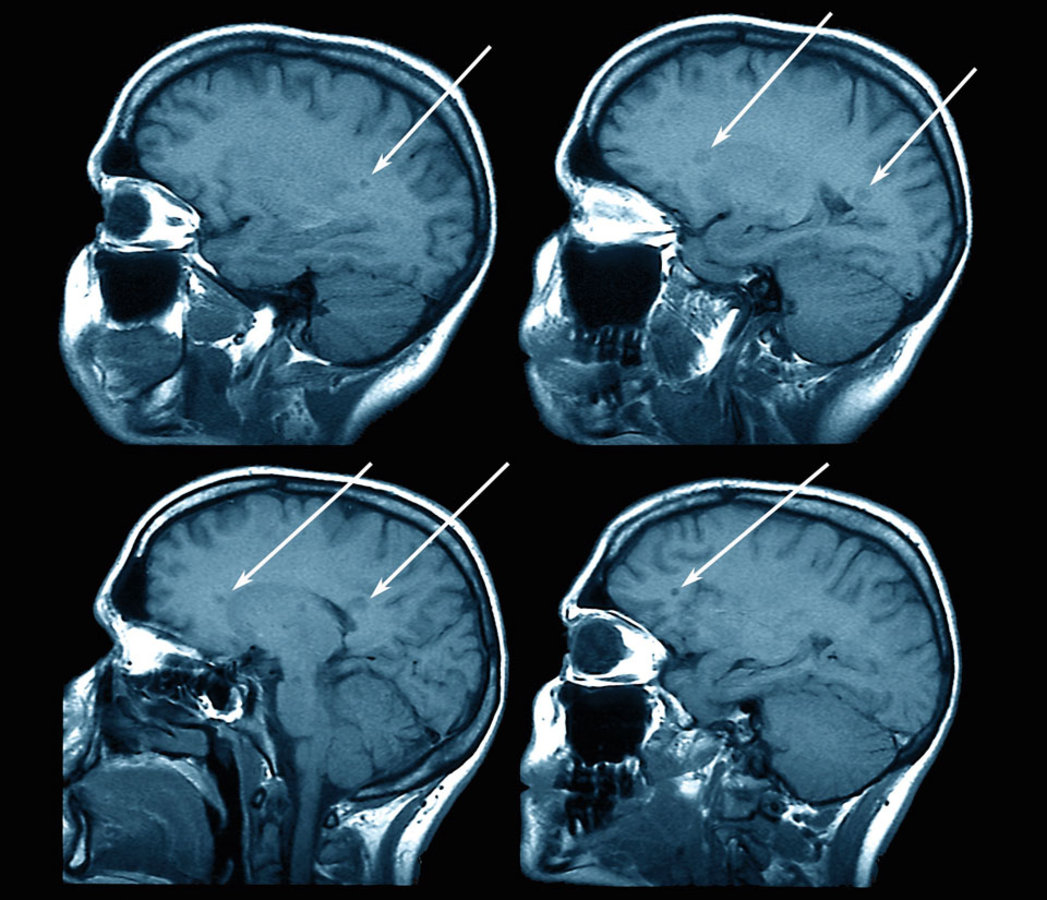

Farbige Magnetresonanztomographie (MRT)-Aufnahmen eines Patienten mit Multipler Sklerose (MS). Farbige Magnetresonanztomographie (MRT)-Aufnahmen eines Patienten mit Multipler Sklerose (MS). © Science Photo Library/Zephyr

Für die Neuroradiologie liegt die Herausforderung darin, das Wechselspiel der neuroinflammatorischen und neurodegenerativen Phänotypen optisch fassbar zu machen, um die Neurologen bei Diagnose, Verlaufskontrolle und Therapiemonitoring zu unterstützen. Damit dies gelingt, sollte die Untersuchung standardisierten Maßstäben folgen, beispielsweise dem Protokoll des Kompetenznetzes Multiple Sklerose oder des Netzwerks Magnetic Resonance Imgaging in MS (MAGNIMS). Das MAGNIMS-Protokoll wurde kürzlich überarbeitet.2 Zu ihm gehören T2-gewichtete, FLAIR- sowie T1-gewichtete Aufnahmen nach Gadoliniumgabe.

Dreidimensionale Sequenzen sind zweidimensionalen deutlich überlegen und sollten wenn möglich angestrebt werden, betonte Prof. Wattjes. „Für die Diagnose reicht 2D häufig aus, vor allem bei pädiatrischen Patienten. Aber wenn Sie 3D akquirieren, können Sie für das Verlaufsmonitoring auf die konventionelle T2-gewichtete Aufnahme verzichten und dadurch das Protokoll verkürzen.“

Diagnostische und differenzialdiagnostische Trennschärfe lassen sich verbessern, indem verschiedene MRT-Kontraste und -Sequenzen kombiniert werden, zum Beispiel FLAIR- plus sensitivitätsgewichtete Aufnahme (SWI). So erhält man einen Mix aus beiden Kontrasten.